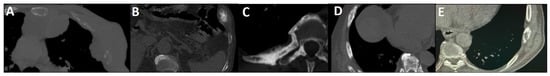

PSMA imaging has transformed the staging landscape of PCa due to its high specificity for PSMA-expressing tumor cells and superior diagnostic accuracy relative to conventional modalities like CT and bone scintigraphy (Figure 4) [128]. By combining molecular imaging (PET) with anatomic localization (CT), this modality facilitates precise lesion characterization and localization. It is particularly valuable in detecting oligometastatic disease and in guiding metastasis-directed therapy [129]. This makes it ideal for guiding metastasis-directed therapies like surgery or radiotherapy and assessing target expression for 177Lu-PSMA-617 treatments [130].

Figure 4.

Partial concordance of PSMA and bone scan. A 66-year-old man with prostate adenocarcinoma (biopsy Gleason score 4 + 5 in 8/12 cores, serum PSA = 45 ng/dL) was referred for staging. Bone scan showed four foci of increased osteoblastic activity, three in the ribs (non-consecutive, anterior/lateral aspect) on the left side as well as L5 vertebra (A). Whole-body 99mTc-PSMA scan SPECT/CT (B) showed PSMA-avid lymph node metastases in the left external iliac and left common iliac (not shown). Skeletal metastases (green arrow) in the L5 spinous process (C) and posterior aspect of the left 2nd rib (D) and lateral 5th left rib (E), and non-PSMA-avid fracture in the 4th left rib (red arrow, (F)). The patient was down-staged from polymetastatic high-volume disease to oligometastatic disease.

Nevertheless, PSMA PET/CT is not immune to false positives. Uptake can occur in benign bone conditions (e.g., Paget’s disease, healing fractures, vertebral hemangiomas), non-prostatic PSMA-expressing tissues (e.g., sympathetic ganglia), and non-PCa malignancies (e.g., colorectal or hepatocellular carcinomas), all of which can complicate image interpretation [18]. These pitfalls underscore the need for correlating imaging findings with clinical context and additional modalities when necessary.